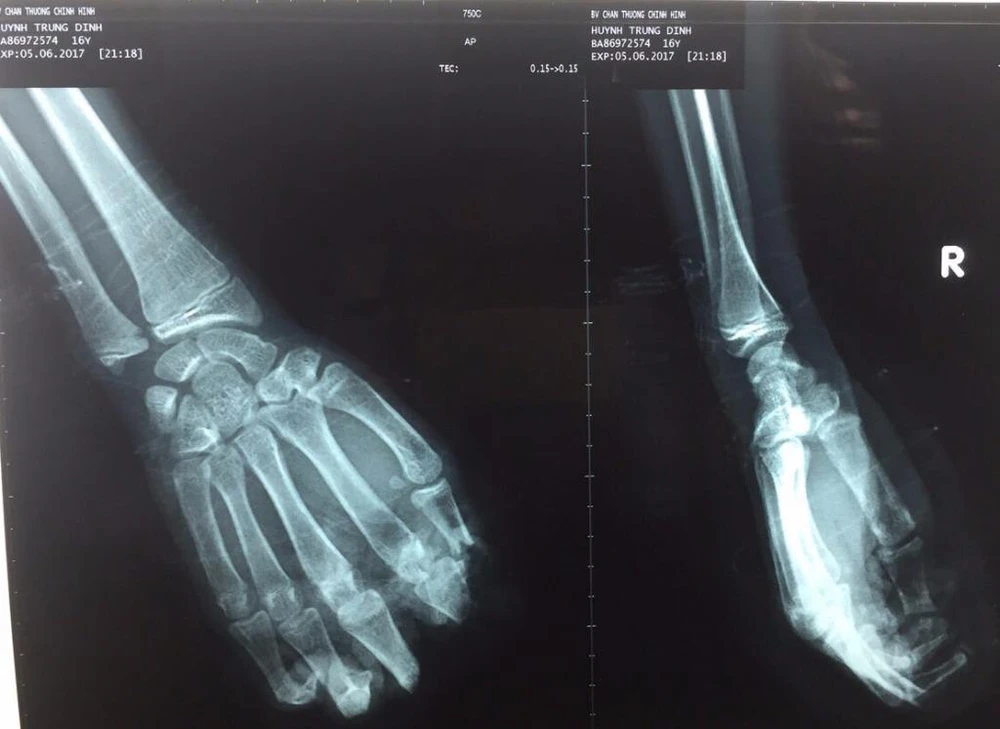

Kết quả chụp X quang cho thấy bốn ngón tay của em D bị đứt lìa.

Kết quả chụp X-quang cho thấy bốn ngón tay của em D. bị đứt lìa. Ảnh: HÒA KHÁNH